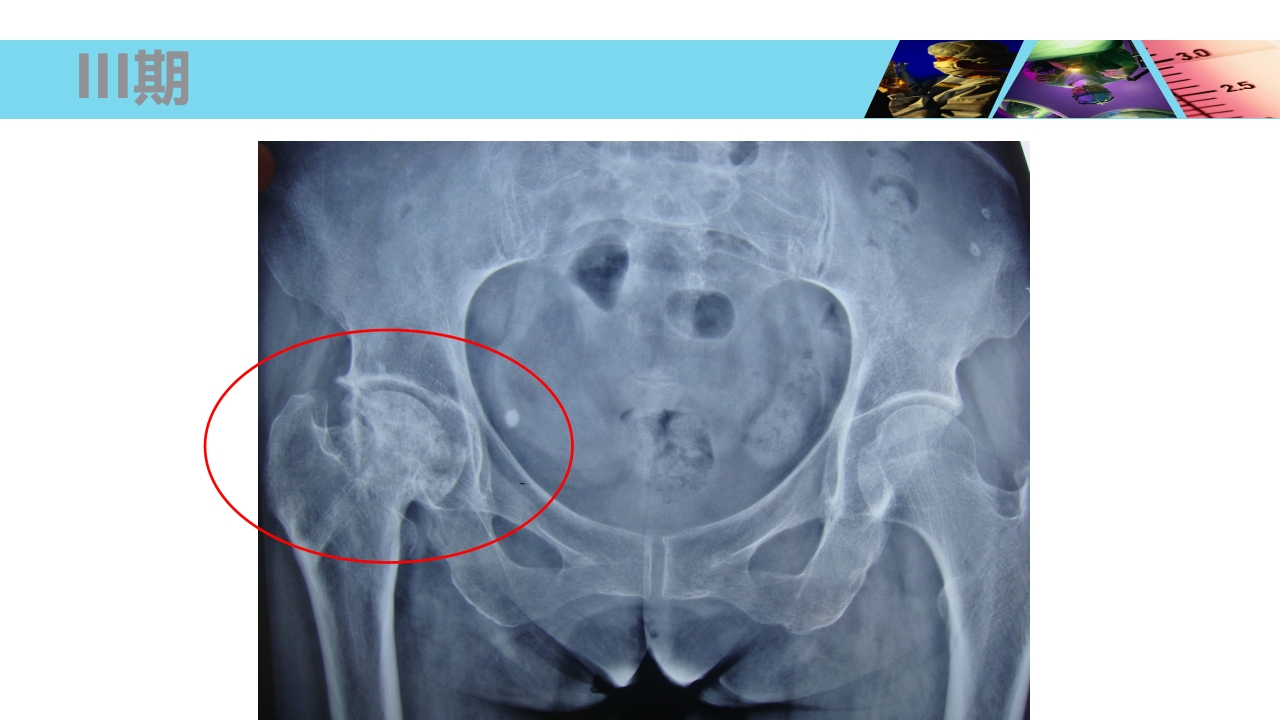

股骨头无菌性坏死 Necrosis of Femoral Head xxxx医院 骨科 WHO/WHAT/WHY/HOW? OUTLINE 1 2 3 4 5 概念及流行病学 病因 发病机制及病理 临床表现及诊断 治疗 概 念 Concept 股骨头坏死、股骨头缺血性坏死、股骨头无菌性坏 死等(Necrosis of Femoral Head) 不同病因破坏了股骨头血供所造成的最终结果。 损伤-修复(Damage-Repair) 4 股骨头血供 由旋股内、外侧动脉所发出的支持带动脉,占股骨头血供的70%。 股深动脉所发出的股骨滋养动脉,占股骨头血供的25%。 闭孔动脉或旋股内侧动脉所发出的股骨头韧带动脉,占股骨头血供的5%。 股骨头血供 一、流行病学 Epidemiology 世界骨科三大难题之一 在美国,年人均发生率在 2 万 -3 万之间,约有 5%-12% 的髋关 节置换...